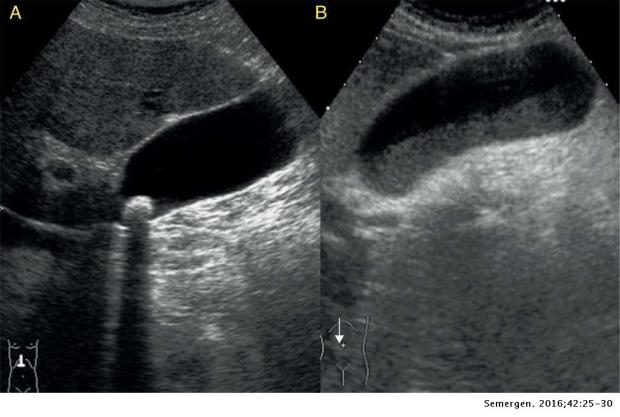

El diagnóstico de colelitiasis se realiza mediante una correcta historia clínica y exploración físicia, apoyándonose en el estudio analítico y radiológico mediante ecografía, donde se observarán las piedras o cálculos en el interior de la vesícula.

La ecografía también sirve para diagnosticar las posibles complicaciones derivadas como la colecistitis, coledocolitiasis o la pancreatitis…, si bien a veces es necesario realizar otras técnicas como una Tomografía Axial Computarizada (TAC) o una Resonancia Magnética Nuclear (RMN)